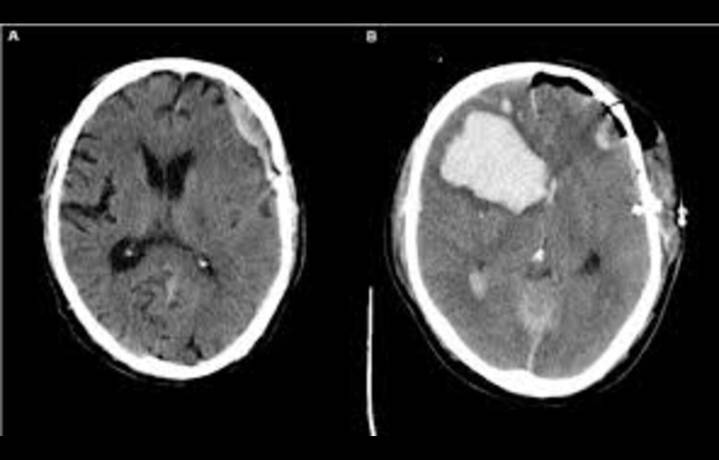

A recent study published in JAMA Network Open examined the outcomes of patients with acute subdural hematoma (ASDH) treated at centers with differing management strategies, comparing those that favor early surgical intervention with those that typically pursue conservative approaches. The authors reported that outcomes in terms of survival and neurological function were broadly comparable between the two treatment pathways. This suggests that patient prognosis may not be determined solely by whether surgical or conservative care is pursued, but also by other clinical and contextual factors such as patient age, comorbidities, injury severity, and access to supportive care.

The study emphasized that acute subdural hematoma is a common and serious form of traumatic brain injury, often requ